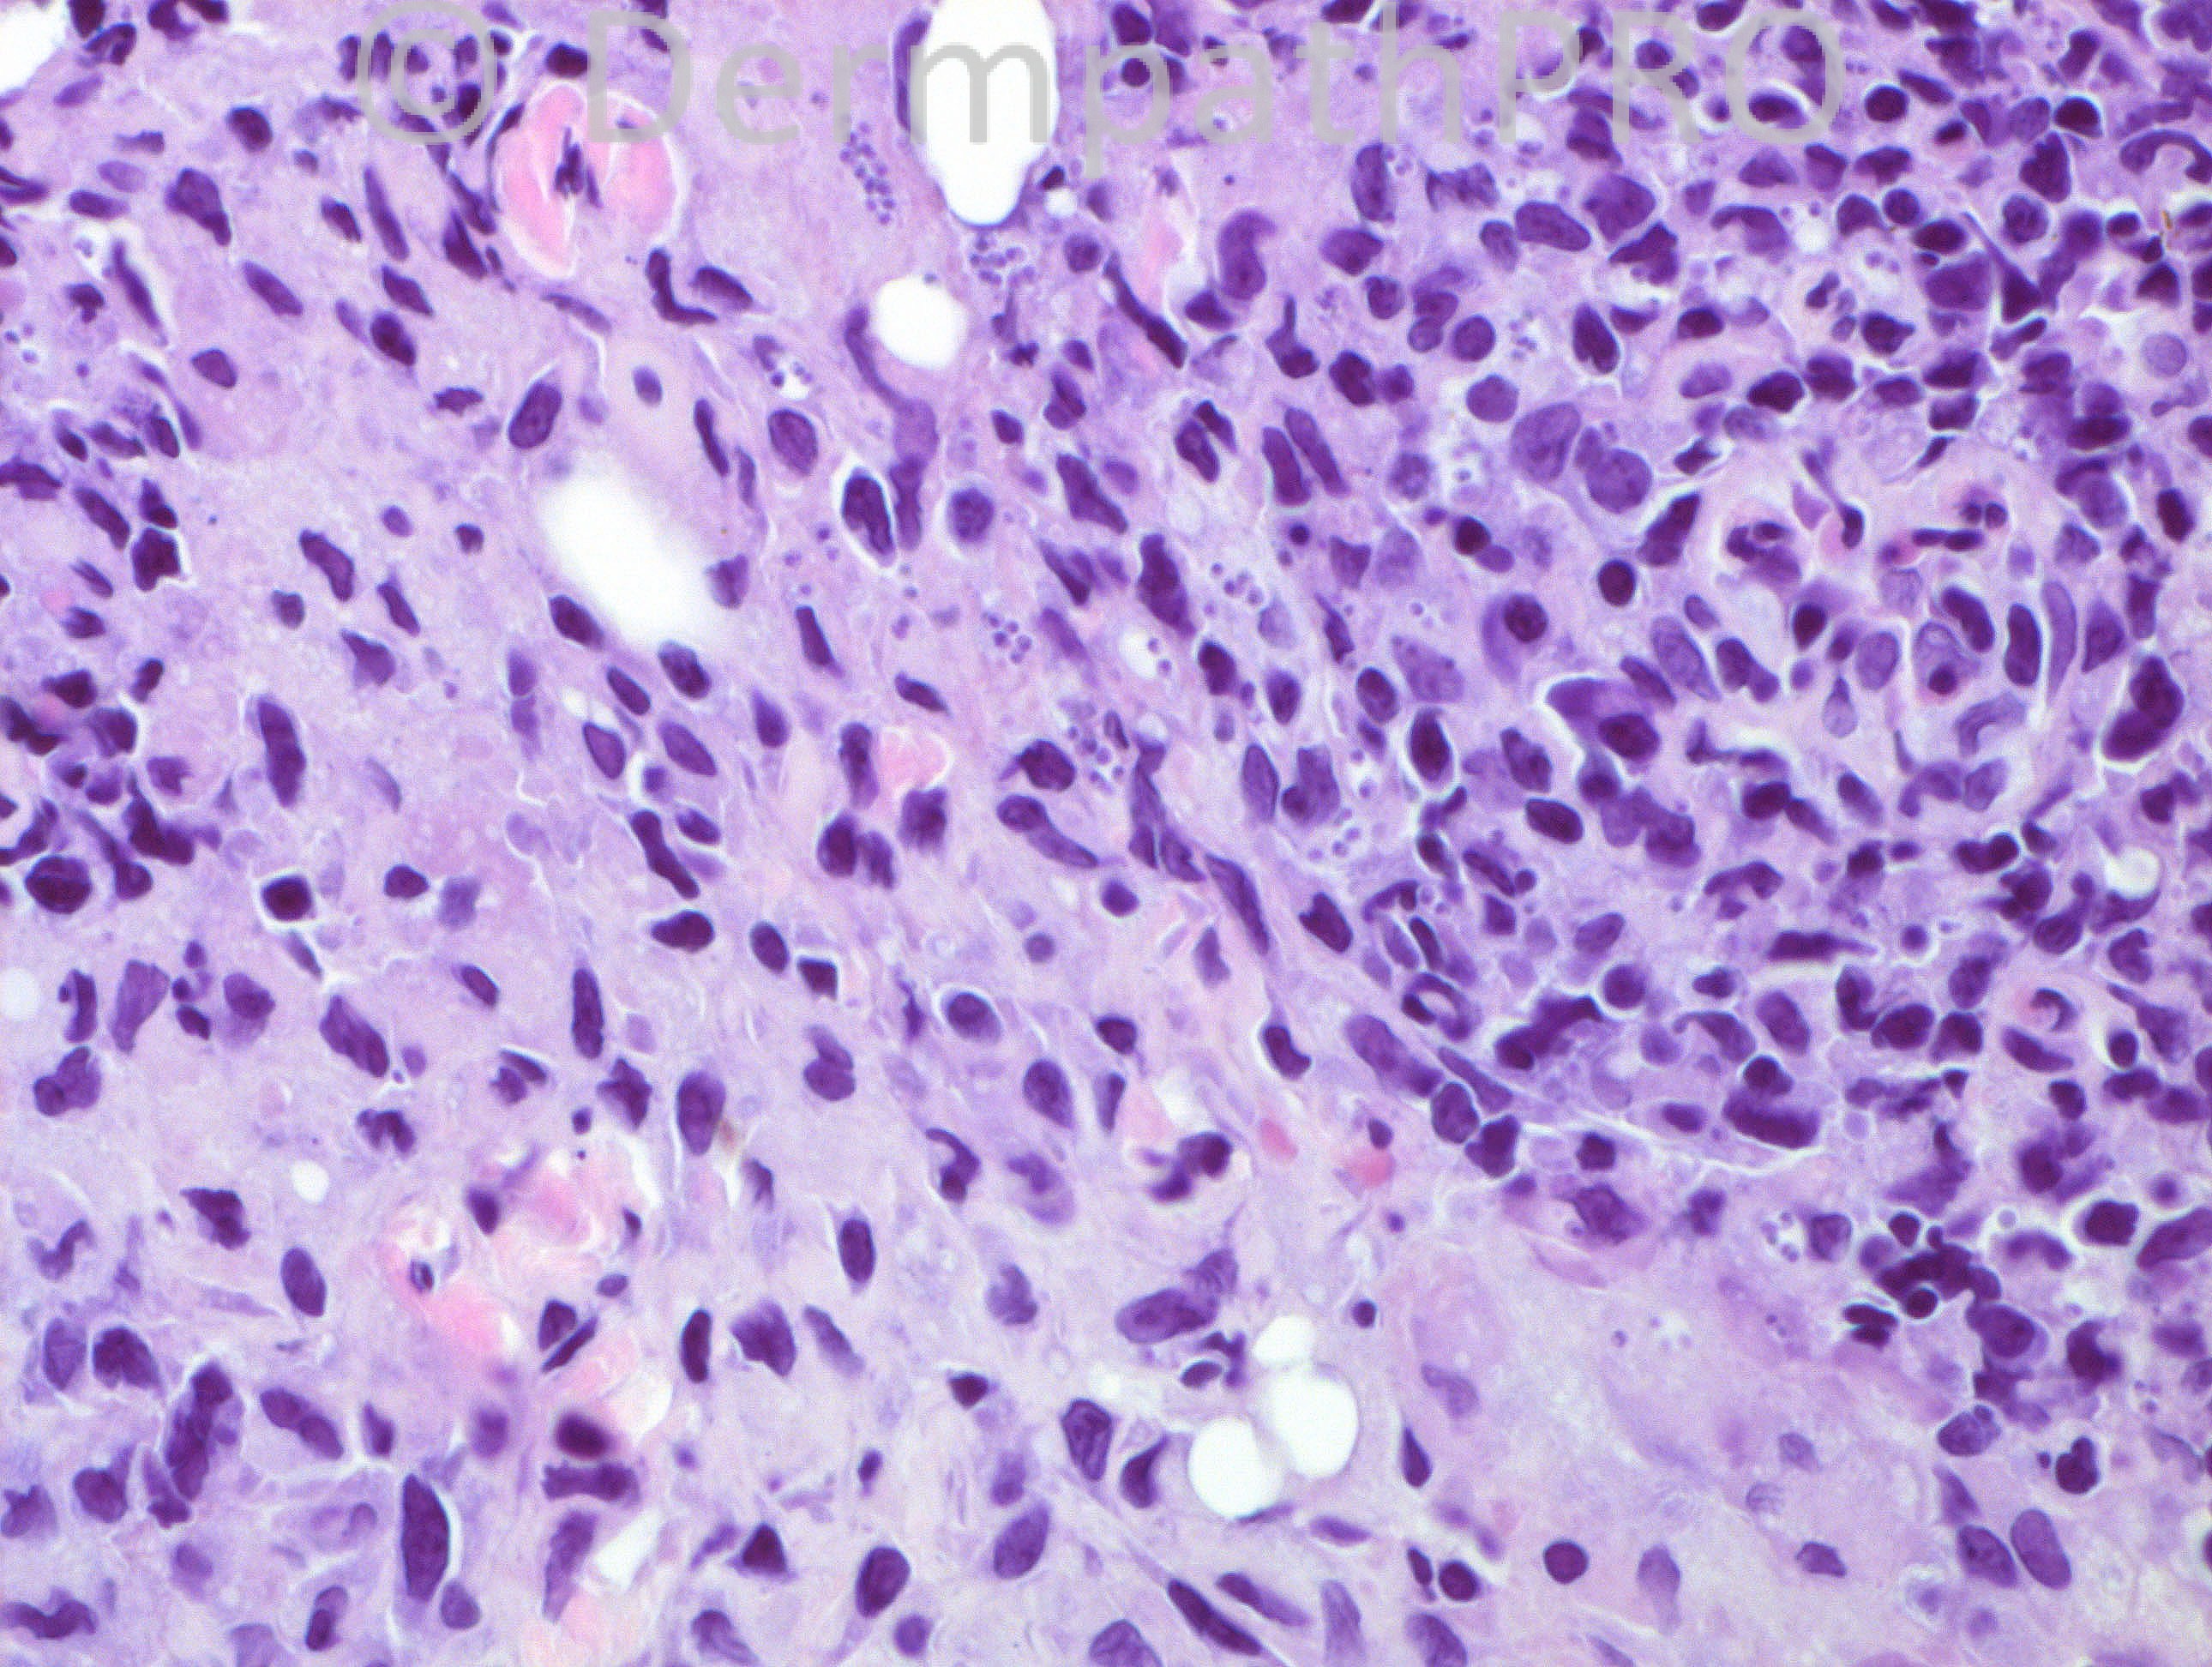

43 years-old hispanic male, with a lesion on his scalp. He developed this lesion some time (exact duration not known) after a “bite†by a “large insect†while in a forest.